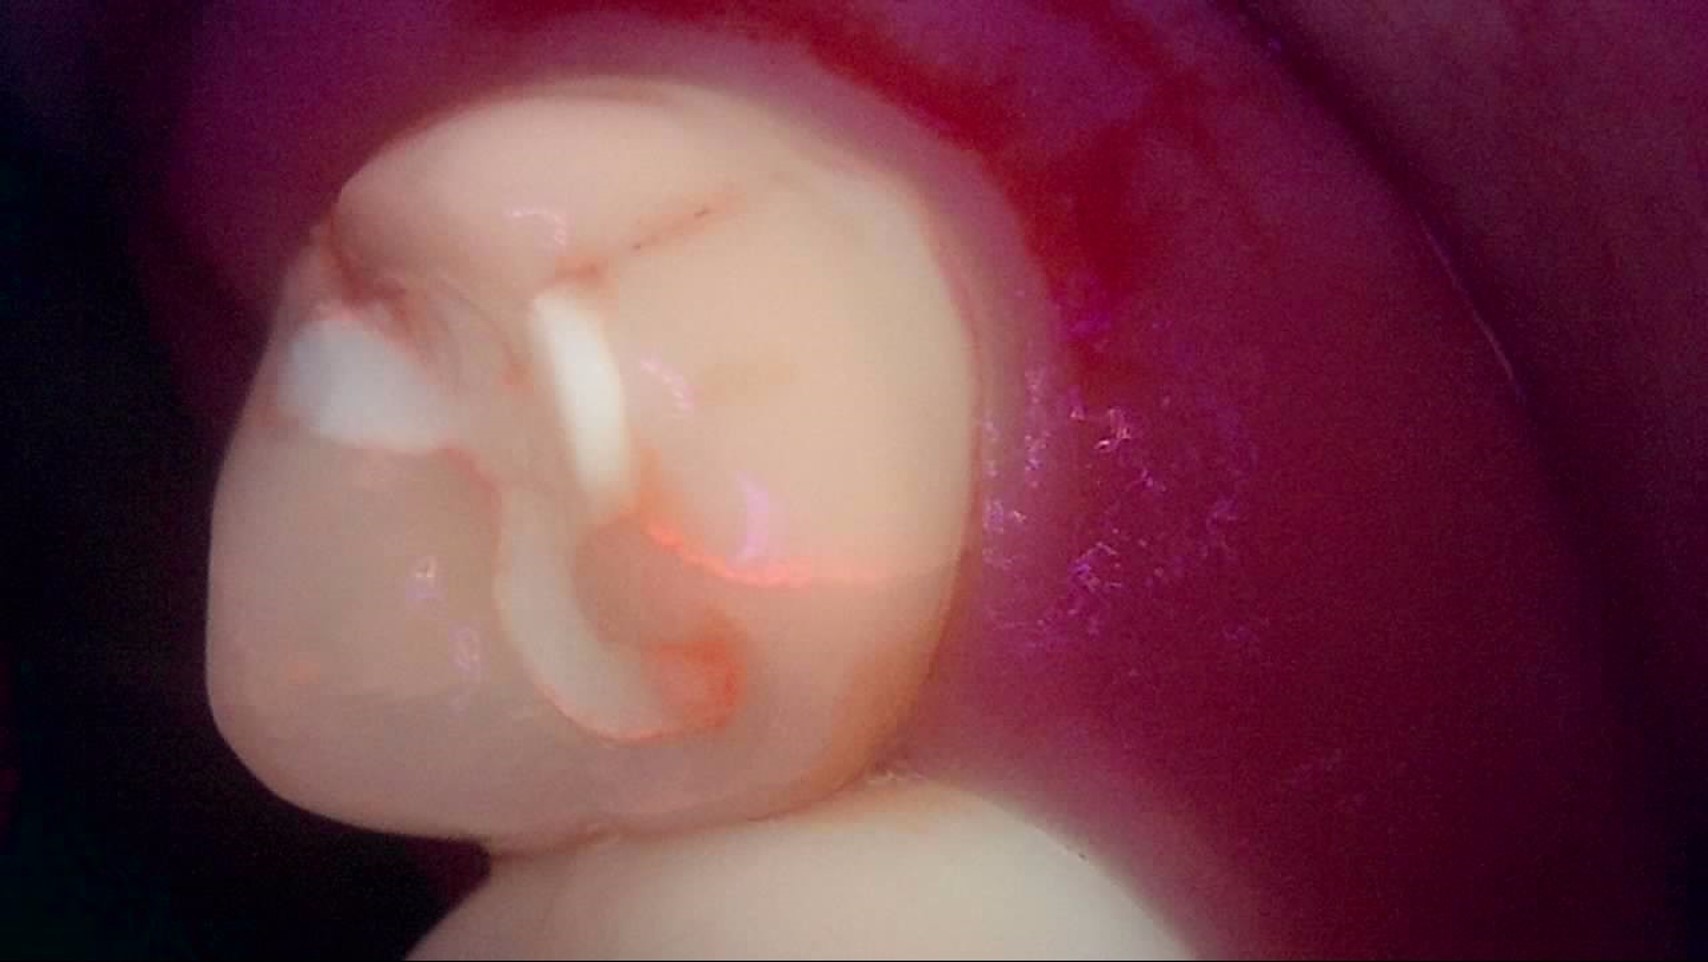

Crack

큐레이캠프로, 큐레이펜씨